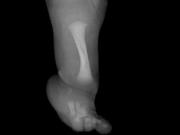

Un niño de nueve años se ha sometido en el Reino Unido a una cirugía pionera para menores para tratar la hemimelia fibular lo que permitirá el desarrollo del peroné y corregir también su estatura.r Esta operación de alargamiento del hueso efectuada por expertos del... + más